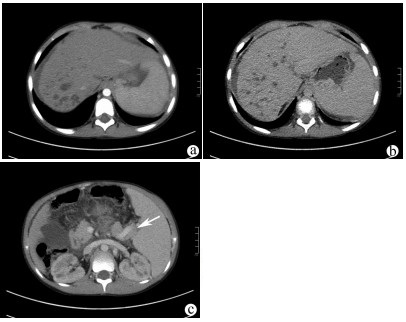

肝脏三维可视化重建技术在儿童复杂肝母细胞瘤肝切除术中的应用价值

赵頔, 叶进冬, 李华丽, 金奎, 刘翔, 李潇然, 段留新, 刘军桂, 吕伟, 段伟宏, 刘全达

2021, 37(9): 2130-2135. DOI: 10.3969/j.issn.1001-5256.2021.09.025

摘要(1333) HTML (406) PDF (3973KB)(68)

摘要:

目的  探讨肝脏三维可视化重建技术在儿童复杂肝母细胞瘤肝切除术中的应用价值。  方法  回顾分析2018年1月—2020年10月于火箭军特色医学中心实施了以根治性切除为目的的肝肿瘤切除术的30例肝母细胞瘤患儿的临床资料,根据术前是否行肝脏三维重建(IQQA-Liver系统)将所有患儿分为三维重建组(n=15)和对照组(n=15),比较2组患儿围手术期临床参数以及短期预后和随访情况。符合正态分布的计量资料2组间比较采用独立样本t检验,不符合正态分布的计量资料2组间比较采用Mann-whitney U检验。计数资料2组间比较采用Fisher确切概率法。  结果  三维重建组较对照组平均年龄更大[(55.7±10.2)月vs (28.2± 2.7)月]、POSTTEXT Ⅲ/Ⅵ期(12例vs 5例)和肝静脉或下腔静脉受累者(11例vs 3例)更多,差异均有统计学意义(P值均<0.05)。所有患儿均顺利完成手术,2组在出血量、手术时间、肝门阻断次数/时间、行肝段及部分肝切除例数方面,差异均无统计学意义(P值均>0.05)。术后中位随访时间9.5个月,三维重建组2例复发,分别于术后10个月和12个月确诊,目前继续化疗中;对照组4例复发,高于三维重建组(P=0.651),其中2例在术后7个月复发接受肝移植存活至今,另有2例复发后短期内死亡。  结论  三维可视化重建技术有助于更安全精准实施复杂儿童肝母细胞瘤肝切除术,尤其是可以使部分POSTTEXT Ⅲ/Ⅵ期患者安全实施扩大肝切除,从而避免行肝移植。